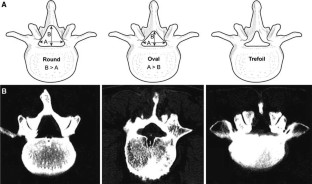

Between January 2008 and December 2009, 144 patients with single-level spinal lumbar stenosis underwent microsurgical bilateral decompression via a unilateral approach by a single surgeon. Patients were categorized into three groups according to spinal canal shape: round (n = 42), oval (n = 36), and trefoil (n = 66), and clinical parameters were assessed both before and after surgery with 2–3 years of follow-up.